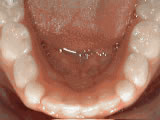

Open bite - Front teeth don't touch

openbite before

Before

openbite after

After

Patient sucked her thumb as a young child. She started treatment at age 13. She had braces and a special appliance — called a crib — to retrain the tongue, for 28 months. Now she can bite the lettuce out of a sandwich..